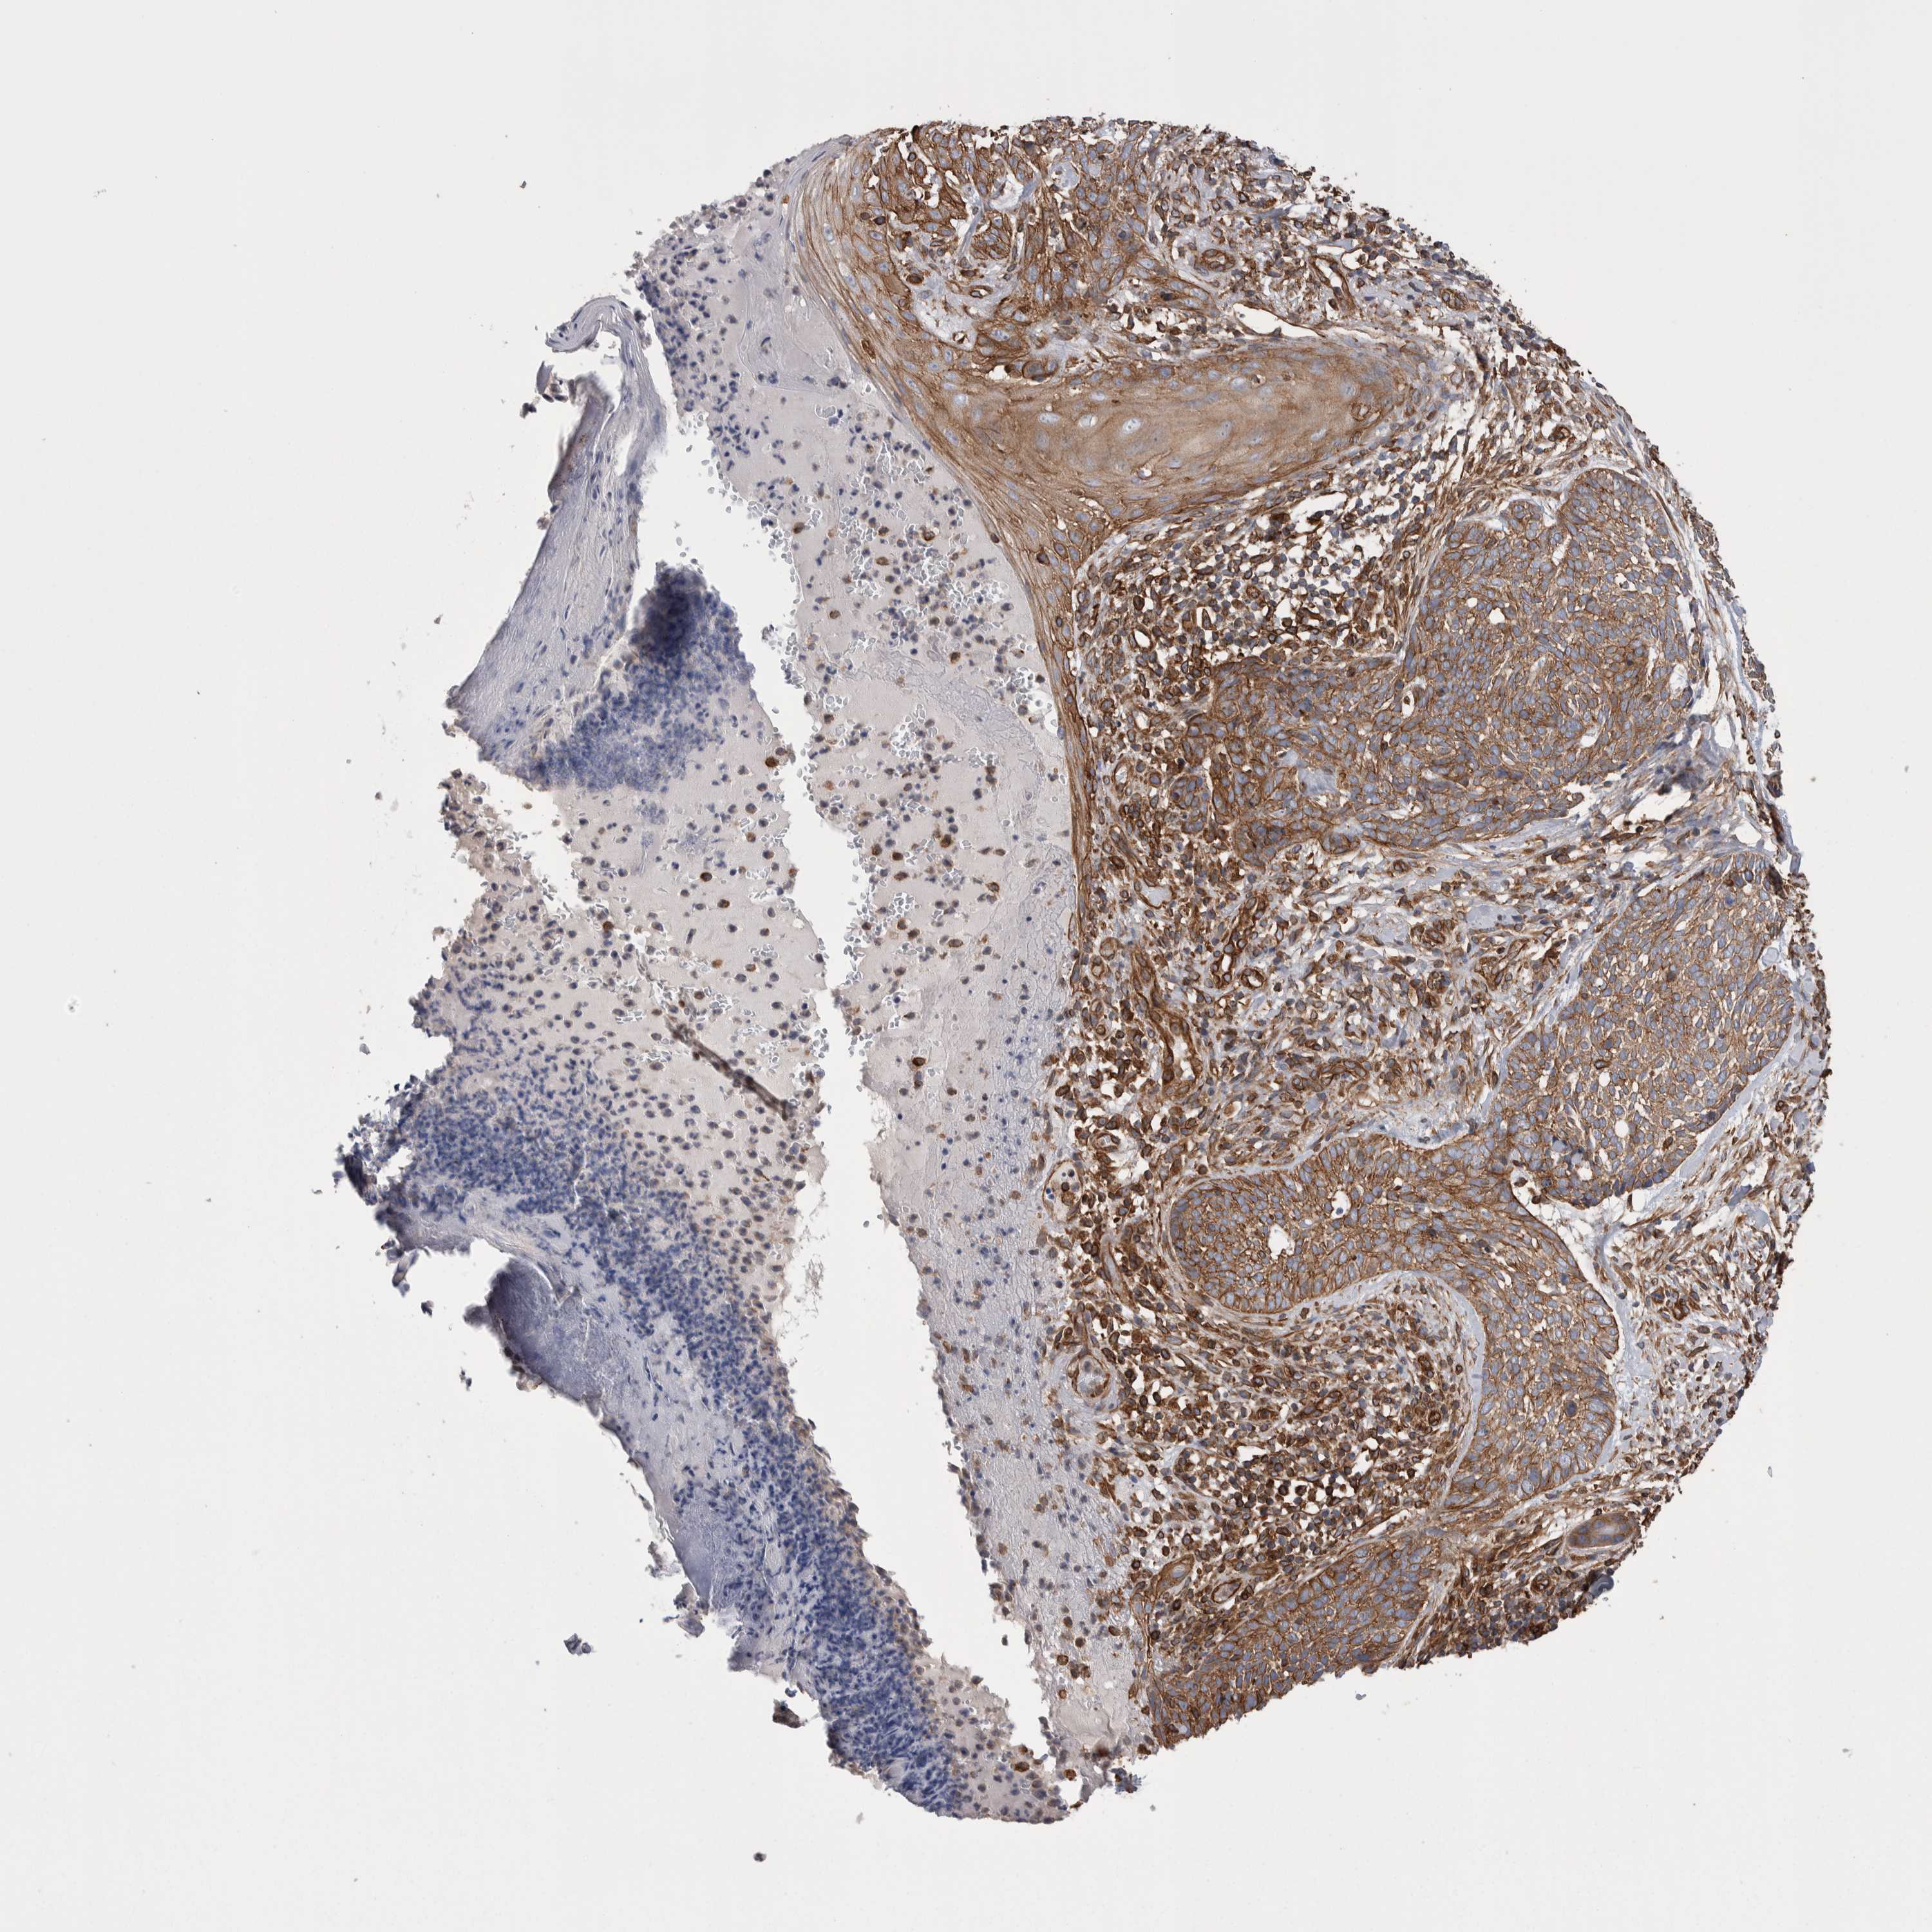

SKIN CANCER - Protein expressioni

A mouse-over function shows sample information and annotation data. Click on an image to view it in a full screen mode. Samples can be filtered based on level of antibody staining by selecting one or several of the following categories: high, medium, low and not detected. The assay and annotation is described here.

Antibody staining in the annotated cell types in the current human tissue is reported as not detected, low, medium, or high, based on conventional immunohistochemistry profiling in selected tissues. This score is based on the combination of the staining intensity and fraction of stained cells.

Each image is clickable and will lead to virtual microscopy that enables deeper exploration of all samples and also displays staining intensity scores, fraction scores and subcellular localization as well as patient and tissue information for each sample.

Antibody HPA024127

Squamous cell carcinoma, NOS